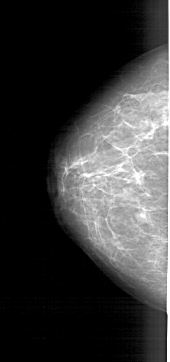

A_1770_1.LEFT_CC

LEFT_CC LINES 5791 PIXELS_PER_LINE 2716 BITS_PER_PIXEL 12 RESOLUTION 43.5 NON_OVERLAY